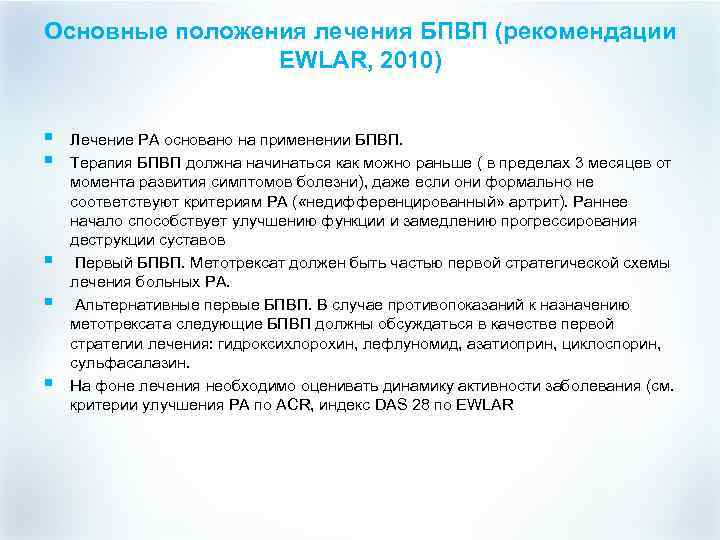

Основные положения лечения БПВП (рекомендации EWLAR, 2010) § § § Лечение РА основано на применении БПВП. Терапия БПВП должна начинаться как можно раньше ( в пределах 3 месяцев от момента развития симптомов болезни), даже если они формально не соответствуют критериям РА ( «недифференцированный» артрит). Раннее начало способствует улучшению функции и замедлению прогрессирования деструкции суставов Первый БПВП. Метотрексат должен быть частью первой стратегической схемы лечения больных РА. Альтернативные первые БПВП. В случае противопоказаний к назначению метотрексата следующие БПВП должны обсуждаться в качестве первой стратегии лечения: гидроксихлорохин, лефлуномид, азатиоприн, циклоспорин, сульфасалазин. На фоне лечения необходимо оценивать динамику активности заболевания (см. критерии улучшения РА по АСR, индекс DAS 28 по EWLAR

Основные положения лечения БПВП (рекомендации EWLAR, 2010) § § § Лечение РА основано на применении БПВП. Терапия БПВП должна начинаться как можно раньше ( в пределах 3 месяцев от момента развития симптомов болезни), даже если они формально не соответствуют критериям РА ( «недифференцированный» артрит). Раннее начало способствует улучшению функции и замедлению прогрессирования деструкции суставов Первый БПВП. Метотрексат должен быть частью первой стратегической схемы лечения больных РА. Альтернативные первые БПВП. В случае противопоказаний к назначению метотрексата следующие БПВП должны обсуждаться в качестве первой стратегии лечения: гидроксихлорохин, лефлуномид, азатиоприн, циклоспорин, сульфасалазин. На фоне лечения необходимо оценивать динамику активности заболевания (см. критерии улучшения РА по АСR, индекс DAS 28 по EWLAR